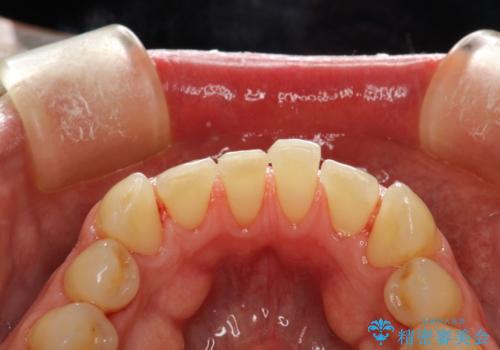

矯正治療終了後にPMTC(Professional Mechanical Tooth Cleaning)

担当医 歯科衛生士